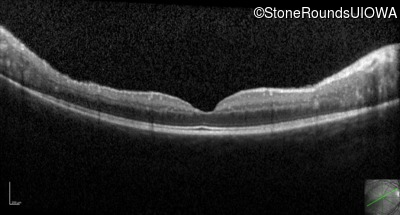

Optical Coherence Tomography - Right - 20/32

Exemplar / OCT Stack

Optical Coherence Tomography - Left - 20/32